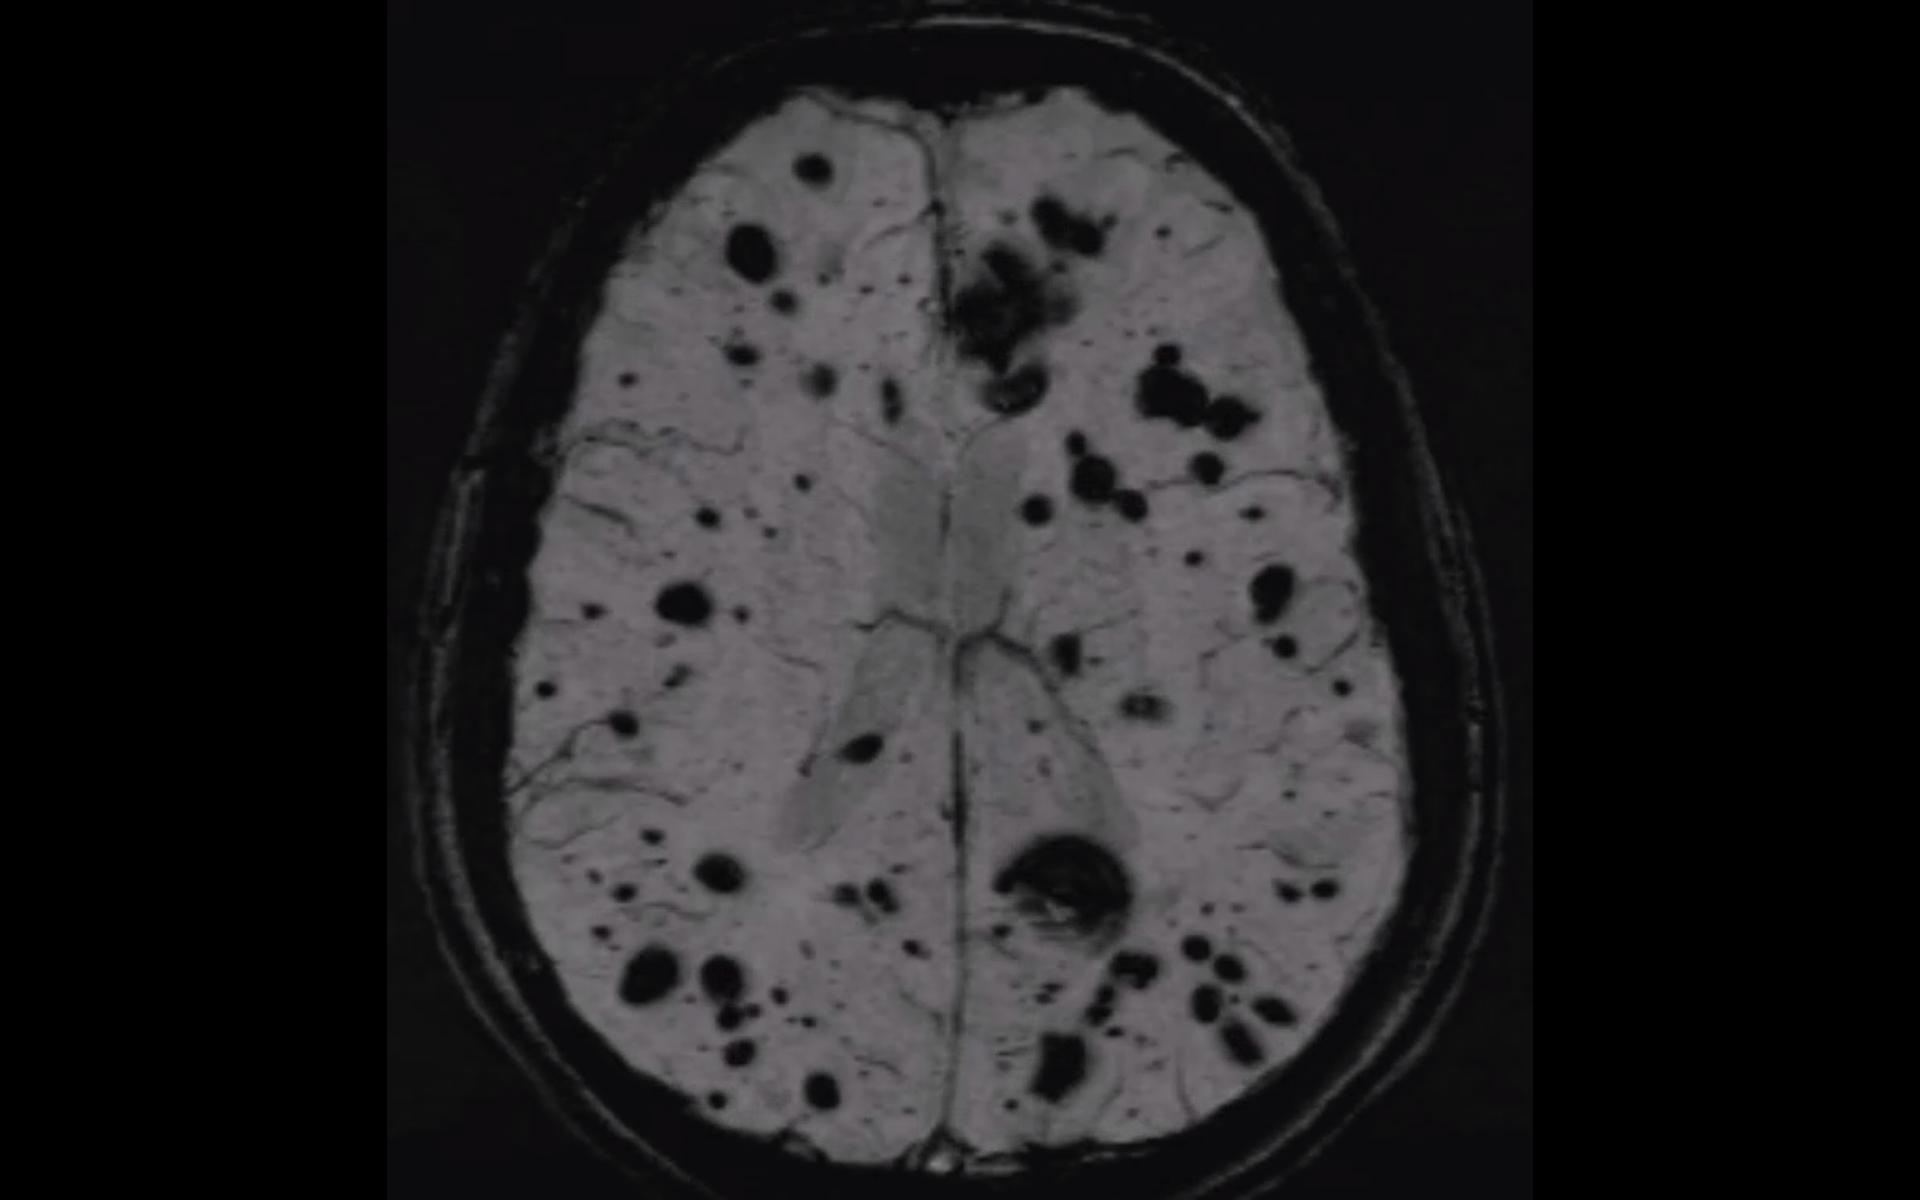

kavernomatose_mri_swi_sequenz.mp4 2.39 MB

- SWI MRT Sequenz eines Patienten mit einer ausgeprägten Kavernomatose.